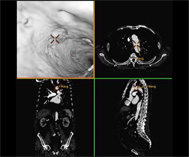

仮想血管内視鏡

MRI装置

日本医科大学付属病院放射線科では3台の1.5テスラMRI装置が運用され、最新鋭の3テスラ装置が稼働を始めます。日常臨床・検査では文字通り頭から足までを対象としたMRI検査が施行され、放射線専門医がCTなどで培った読影力とともにMRIの基礎や利点などを考慮してMRI画像を読影しています。この専門医の中には米国有名大学や国内の脳神経センターに留学した経験を有するスタッフもいます。